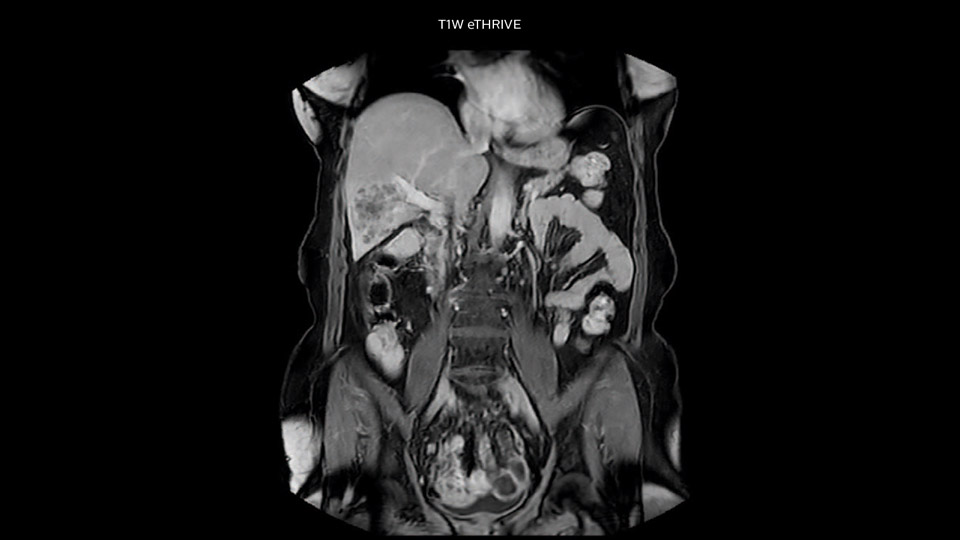

In this example the image quality of the MultiVane XD images is evidently better than in the images without MultiVane XD. Ingenia 1.5T with dS Torso coil solution.

“Our liver exams are quite fast,” says Dr. Baumann. “If the patient tolerates it, we use an arms-up position to reduce the FOV and speed up the exam with dS SENSE.” “We acquire one transversal high resolution T2-weighted sequence with 3 mm slice thickness, for example for pancreas or liver lesions. Then we also add a T2 fat suppressed MultiVane XD SPIR sequence. We perform these two routinely in our liver imaging. We use high dS SENSE factors to significantly shorten scan times to 2-4 minutes, which can improve our protocol; it’s a very robust scan.” “We include mDIXON for the dynamic sequences because of the robust and homogeneous fat suppression we get with that. We had been using eTHRIVE, but we are now quite happy with mDIXON. Sometimes we use a medication to calm the bowels, to further improve the image quality.”